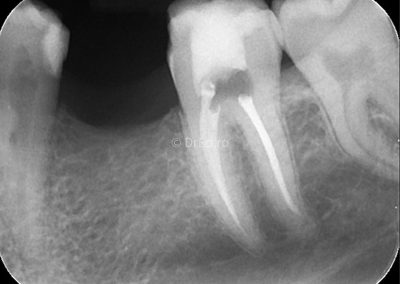

Galerie

Toate imaginile, fotografiile și radiografiile publicate pe acest site sunt protejate prin drepturi de autor și constituie proprietatea exclusivă a Dred.ro.

Aceste materiale sunt furnizate exclusiv în scop informativ și educațional și nu conțin date cu caracter personal sau informații care permit identificarea pacienților, în concordanță cu legislația privind protecția datelor cu caracter personal și GDPR.

Reproducerea, copierea, distribuirea, publicarea, transmiterea, modificarea sau orice altă utilizare, integrală ori parțială, a acestor materiale, în orice formă și prin orice mijloace, fără consimțământul prealabil scris al titularului drepturilor, este strict interzisă și poate atrage răspunderea civilă și/sau penală, în condițiile legii aplicabile privind drepturile de autor și protecția proprietății intelectuale.